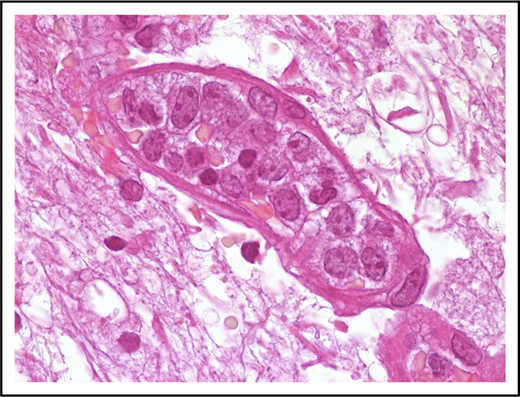

Neoplastic cells are in most instances large with high nuclear/cytoplasmic ratio and scant cytoplasm (Figure 1). Nuclear outline is usually smooth, less often with irregular contour.

Morphological features of IVLBCL. A blood vessel lumen filled mainly with large B neoplastic lymphocytes, mostly resembling centroblasts. Hematoxylin-and-eosin stain; original magnification ×1000.

Isolated cases characterized by smaller cells with irregular nuclear profiles have been reported.3 The nucleolus may be single and prominent or multiple nucleoli may be readily recognizable. IVLBCL, therefore, shows a morphological spectrum ranging from centroblasts to immunoblasts/plasmablasts,3,7,8 including rare forms with anaplastic morphology.9 The blood vessel lumen is not only certainly the diseases’ vehicle but also its site of active replication, as confirmed by the presence of mitotic figures and the high proliferative index highlighted by Ki-67 immunostaining. With the theoretical exception of major vessels, almost all blood vessels could be involved by IVLBCL.3 Different growth patterns may be recognized in this type of lymphoma and usually coexist in the same sample or patient. In the “discohesive” pattern, IVLBCL cells are preferentially within the central portion of the blood vessels and exhibit a free-floating appearance, whereas in the “cohesive” pattern neoplastic cells almost completely fill the lumen and assessment of the vascular structure tends to be difficult. The less frequent pattern is named “marginating” because tumor cells preferentially adhere to endothelia leaving the central portion of the lumen free.10 Cases of IVLBCL associated with hemophagocytosis are accompanied by nonneoplastic histiocytes filled with red cells or mononuclear cells. Cells with phagocytic activity may be readily visible in peripheral blood smears (see “Hemophagocytic syndrome-associated variant”).